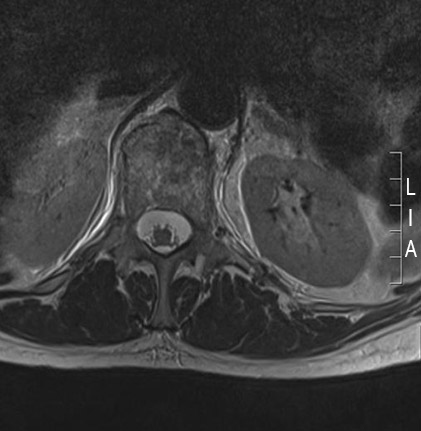

IRM de la columna lumbar: vista transversal (secuencia ponderada en T2) con fractura osteoporótica del cuerpo vertebral T12

De la colección personal del Dr. B. Nurboja y D. Choi